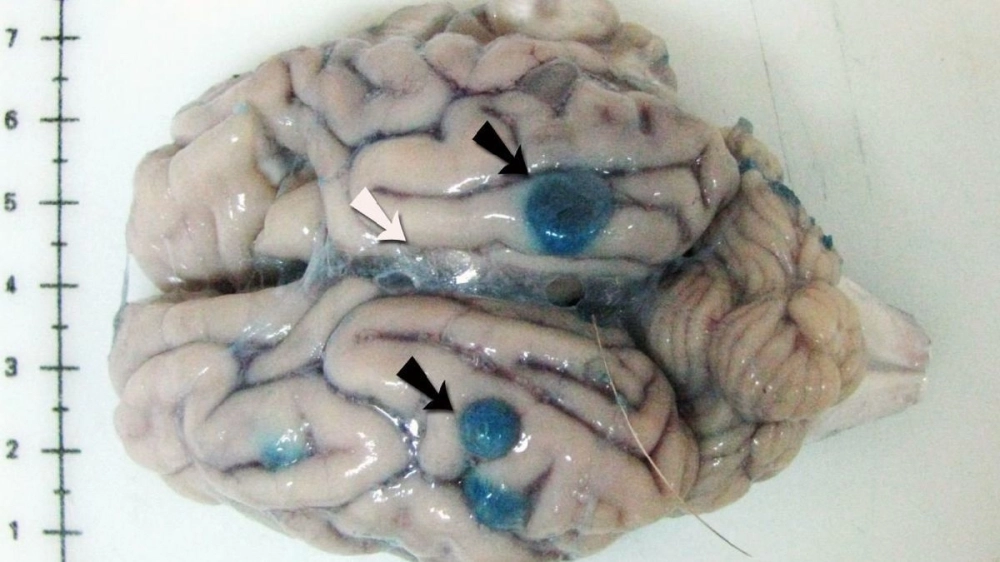

মুম্বইয়ের স্নায়ুরোগ বিশেষজ্ঞরা জানাচ্ছেন, বর্ষাকালে অনেকেই খাদ্যসুরক্ষা সংক্রান্ত সাধারণ নিয়ম মানেন না। তার ফলেই এই সংক্রমণের আশঙ্কা বেড়ে যায়। পেটে ঢুকে এই ডিম রক্তনালীর মাধ্যমে মস্তিষ্কে পৌঁছে যায় এবং সিস্ট তৈরি করে, যার ফলে শুরু হয় খিঁচুনি, ক্রমাগত মাথাব্যথা। চিকিৎসা সময় মতো শুরু না হলে স্নায়বিক অক্ষমতাও দেখা দিতে পারে।

এই রোগকে অনেকেই মৃগীরোগ বলে ভুল করেন। ফলে সঠিক সময়ে এমআরআই বা সিটি স্ক্যান না করালে রোগ ধরা পড়ে না। চিকিৎসকরা জানাচ্ছেন, নিউরোসিস্টিসারকোসিসের উপসর্গ অনেক সময় ম্যালেরিয়া বা ভাইরাল ফিভারের সঙ্গেও মিলে যেতে পারে, তাই সঠিক রোগ নির্ণয় না করে চিকিৎসা শুরু করলে জটিলতা আরও বাড়তে পারে।